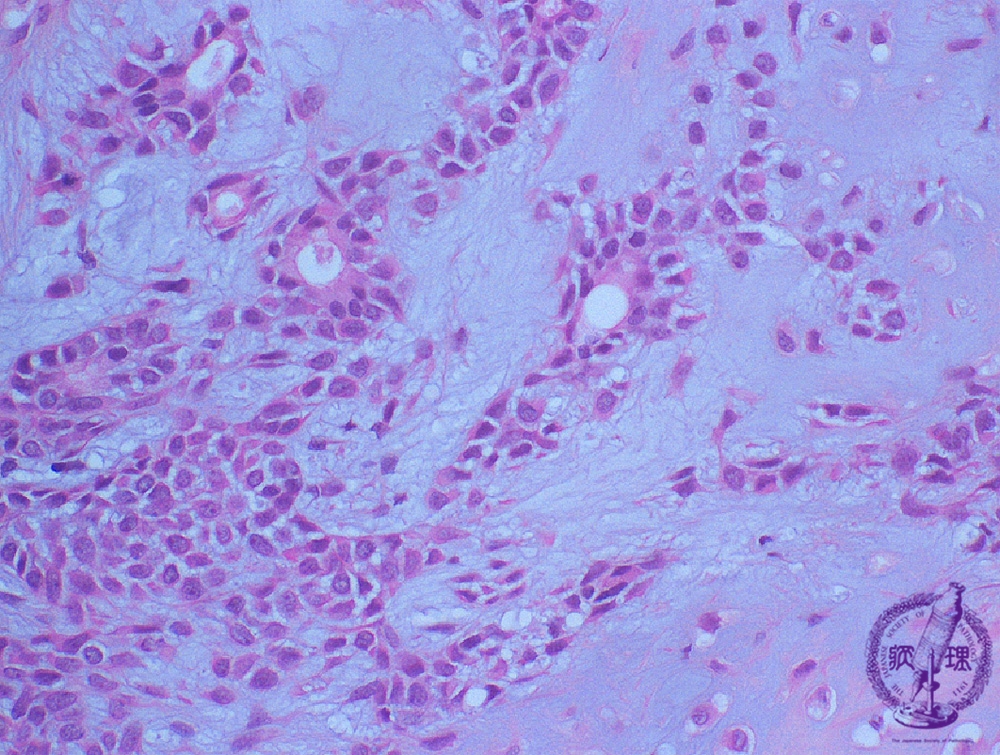

Microscopic finding (HE stain, high-power view):The lumen (*) is lined by glandular epithelial cells, below which are neoplastic myoepithelial cells and a transition to widened intercellular spaces containing mxyoid and chondroid matrices.